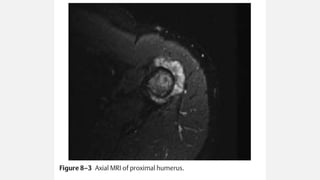

MRI

• The best imaging modality to measure the

• Extent within the bone & soft tissue

• Determine relationship to nearby anatomic structures

• Superior to CT for evaluation of invasion of muscle, neurovascular

structures, adjacent fat planes and the degree of marrow involvement

• Superior in assessing intra-articular extension and the presence of intra-

tumoral necrosis and hemorrhage

• Osteosarcoma lesion is usually dark on both T1W and T2W images

because of the osseous matrix

OSTEOSARCOMA PROXIMAL HUMERUS

• A 6-year-old female presents with a 2-month history of pain in her right

shoulder.

• This pain has become increasingly severe, and she is now no longer

using her arm normally.

• X- ray at presentation included a plain film of the humerus.

Orthopedic Oncology by Ernest Conrad